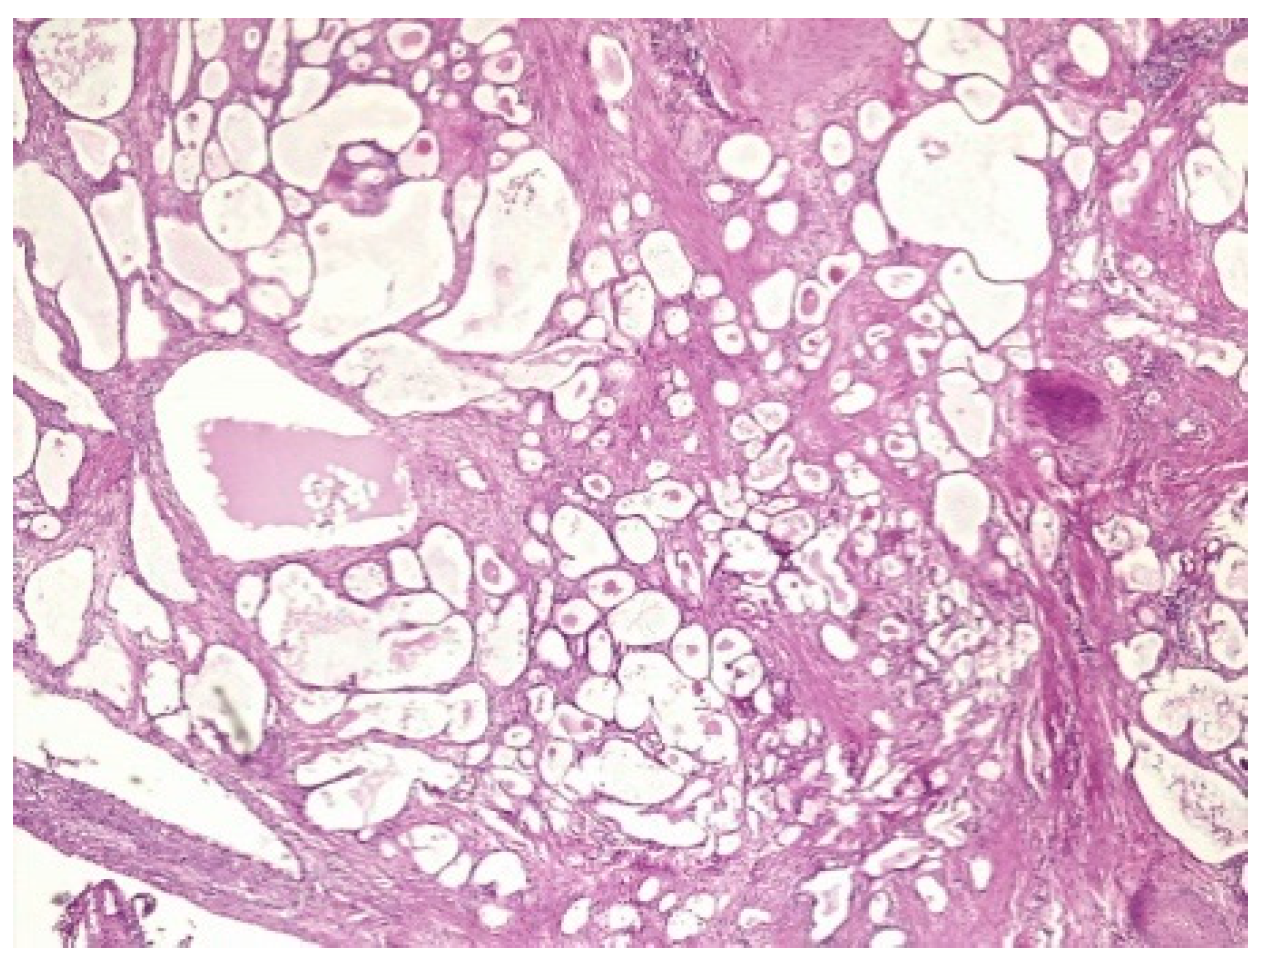

| LEEP | atypical mesonephric hyperplasia with a malignant transformation zone—mesonephric adeno-carcinoma with moderate cell pleomorphism, moderate mitotic activity, without invasion of the lymphovascular space, resection limits tangential to the lesion |

| Radical vaginal trachelectomy with laparoscopic pelvic lymphadenectomy | Uterine isthmus—endocervix—upper limit of resection with benign mesonephric hyperplasia with areas of atypical mesonephric hyperplasia, showing moderate atypia; |

| Cervix with previous conization –appearance of atypical mesonephric hyperplasia; zone of stromal invasion and malignant transformation—endocervical mesonephric adenocarcinoma with moderate cell pleomorphism and mitotic activity, intraluminal detritus, added inflammation | |